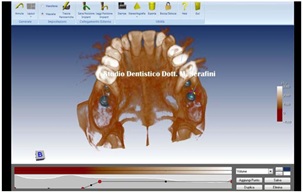

TC left side shown in figure 30.

Figure 30: TC left Side.